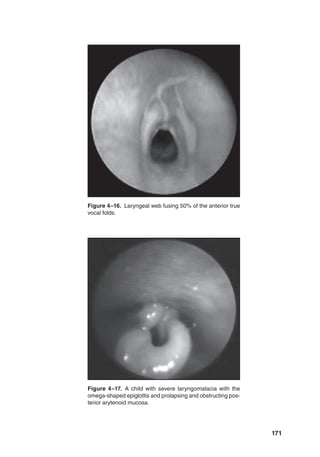

bilateral motor activity and proper sequenc-

ing of the muscles involved in swallowing.

Prevention of competing muscle activities,

for example, speech and respiration, allows

completion of the complex motor act of

deglutition without interruption (Kennedy